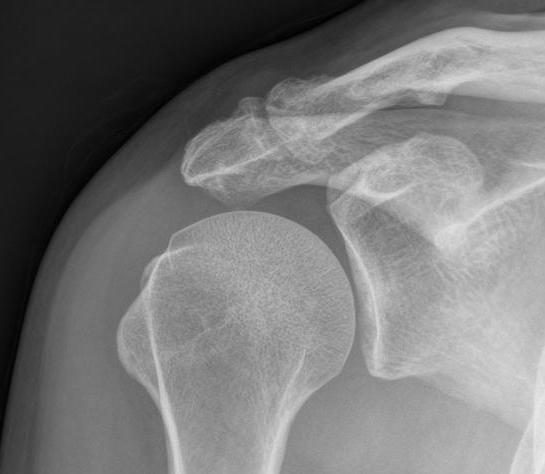

Xray

Zanca view - AP 10° cephalic tilt with 50% penetration

Acromioclavicular osteoarthritis

Stein et al. J Should Elbow Surg 2001

Grade I: Normal

Grade II: Capsular distension, bone marrow edema, mild joint narrowing

Grade III: Capsular distension, joint space narrowing, marginal osteophytes

Grade IV: Markedly abnormal ACJ with large osteophytes